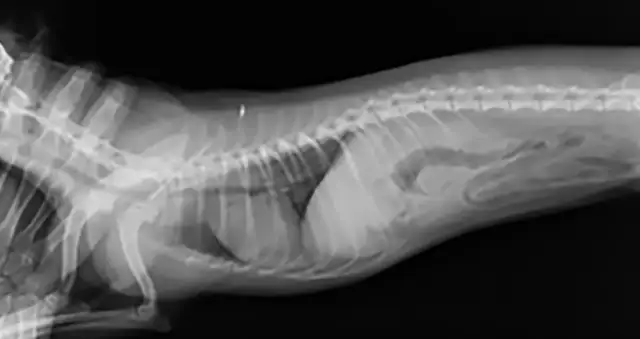

Veterinary nurses taking thoracic radiographs must remember that radiation safety comes first. Appropriate personal protective equipment should be used. Hands in the primary beam are unacceptable and dangerous. (See Figures 1 & 2.)

Figure 1 Ventrodorsal view obtained while holding the patient’s thoracic limbs with the hands

Images courtesy of Janet Paquette, AS, LVMT